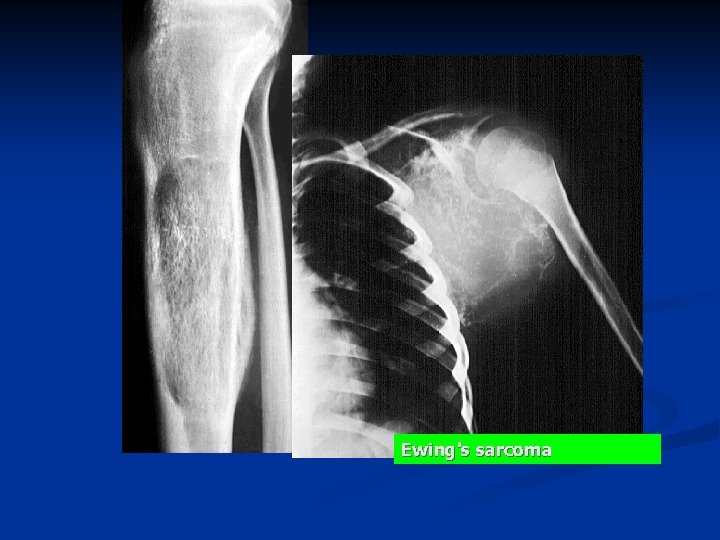

n Ewing's sarcoma may occur in any bone but most frequently involves long bones. n n Femur (27%), pelvic bones (18%), tibia and fibula (17%), humerus (10%), scapula (6%). Radiology: A mottled "moth eaten" destructive lesion in the diaphysis n periosteal reactive new bone n n sometimes formed in concentric layers and producing an "onion skin" appearance, and often accompanied by a soft-tissue mass.

Ewing's sarcoma